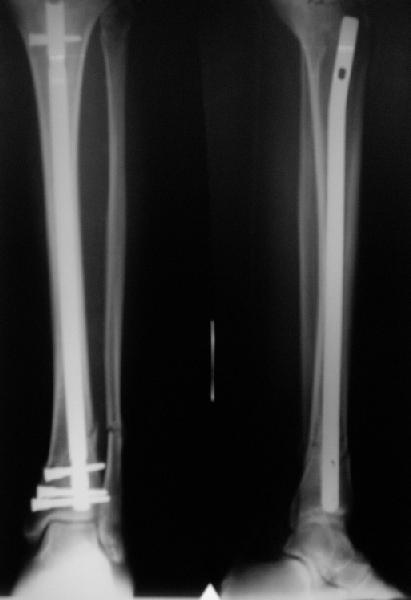

A typical case is attached, also an image with intra-op reduction obtained by a small wire distractor, in the moment of insertion a Poller wire in AP direction. Fixation by a SIGN nail. Despite the fibula was not fixed healing was obtained with the unchanged alignment.

Very interesting application, but is the final position in a little distal varus with some fibula

distraction? Would that have been eliminated by fibula plating?

TDVC> Very interesting application, but is the final position in a

TDVC> little distal varus with some fibula distraction?

At least both the ankle mortise and tibial alignment look acceptable, don't they?

TDVC> Would that have been eliminated by fibula plating?

I am just trying to illustrate that prevention of 1)tibial valgus and 2)loss of reduction can be provided without fibular plating. Small changes of conventional nailing techniques allow to maintain reduction of the tibia reliably without adjunctive fibular stabilization.